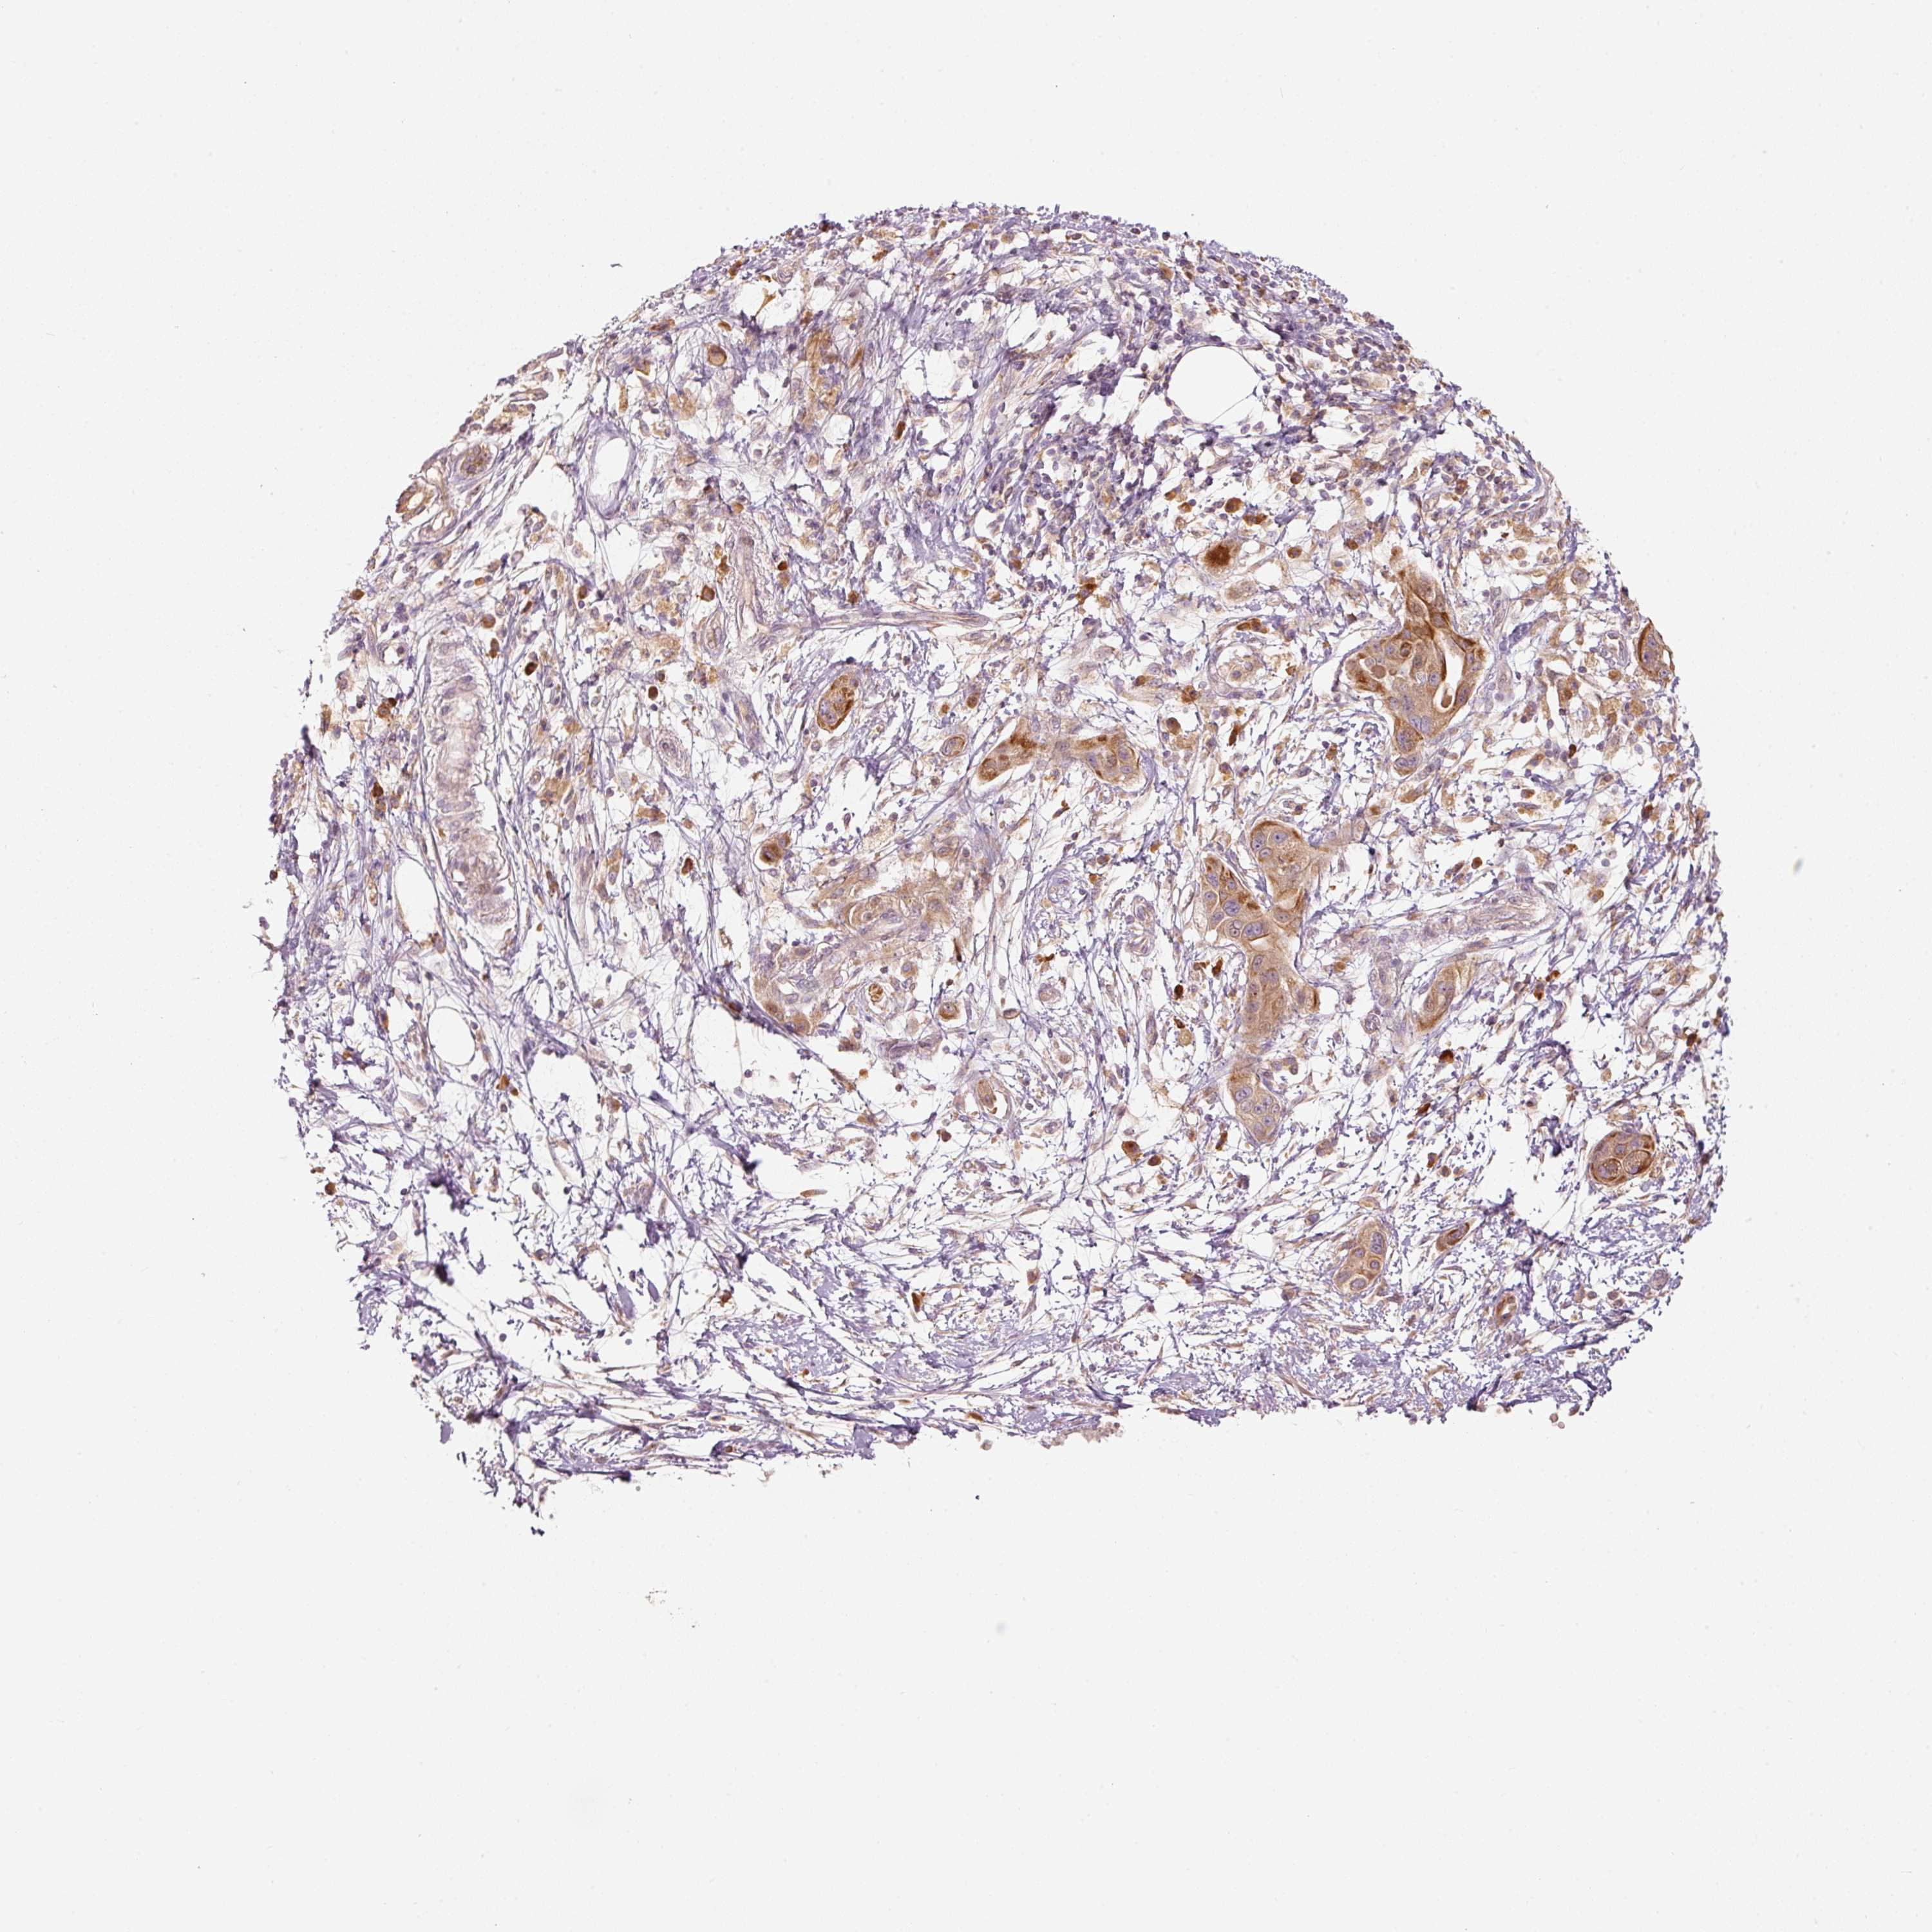

PANCREATIC CANCER - Protein expressioni

A mouse-over function shows sample information and annotation data. Click on an image to view it in a full screen mode. Samples can be filtered based on level of antibody staining by selecting one or several of the following categories: high, medium, low and not detected. The assay and annotation is described here.

Note that samples used for immunohistochemistry by the Human Protein Atlas do not correspond to samples in the TCGA dataset.

Antibody stainingi

Antibody staining in the annotated cell types in the current human tissue is reported as not detected, low, medium, or high, based on conventional immunohistochemistry profiling in selected tissues. This score is based on the combination of the staining intensity and fraction of stained cells.

Each image is clickable and will lead to virtual microscopy that enables deeper exploration of all samples and also displays staining intensity scores, fraction scores and subcellular localization as well as patient and tissue information for each sample.

Antibody HPA052496

Staining

High

Medium

Low

Not detected

Intensity

Strong

Moderate

Weak

Negative

Quantity

>75%

75%-25%

<25%

None

Location

Nuclear

Cytoplasmic/membranous

Cytoplasmic/membranous,nuclear

Adenocarcinoma, NOS